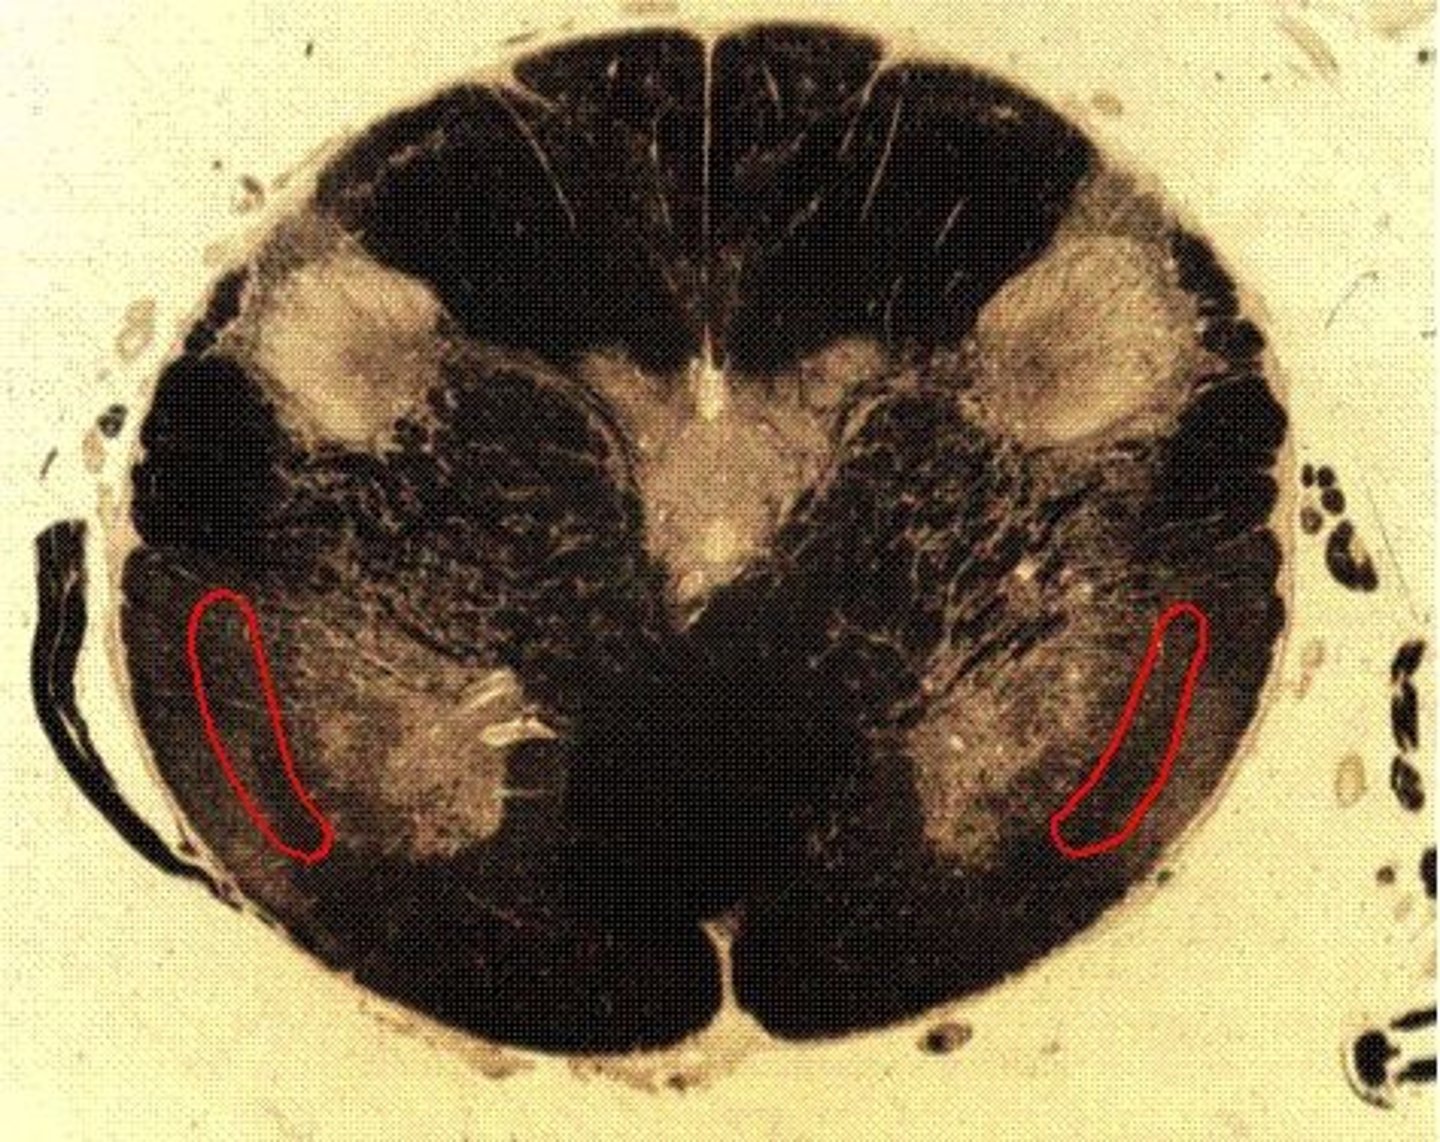

grey matter

(in orange)

dorsal horn

lateral horn

ventral horn

dorsal median sulcus

ventral median fissure

grey commissure

central canal

white matter

dorsal column

lateral column

ventral column